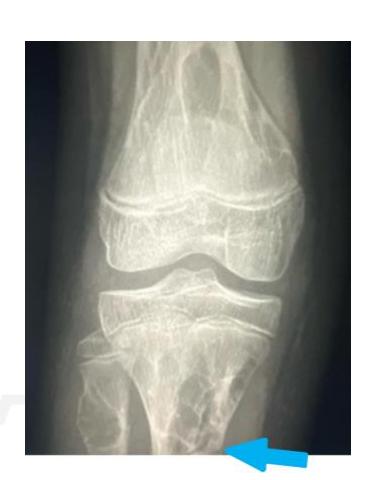

Q8/ What is the type of fracture shown in these pictures?

- A- Salter harris fracture II